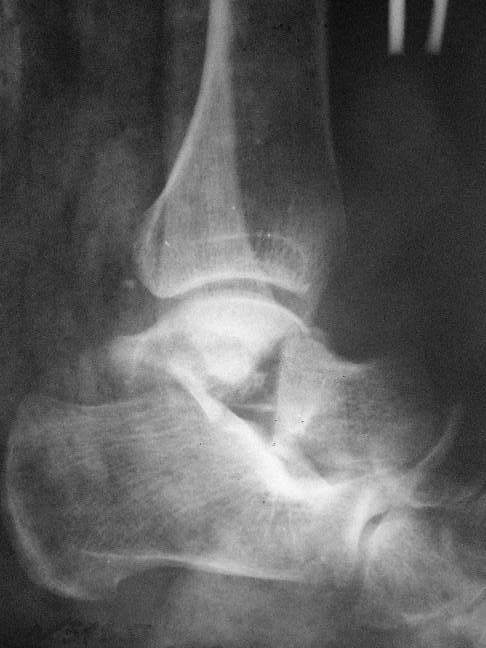

Перелом таранной кости

Прошу коллег помочь советом. 3 дня назад поступила пациентка 23 года с переломом шейки ладьевидной справа, переломом лодыжек и заднего края б/берцовой кости со смещением и подвывихом кзади, переломом внутреннего мыщелка правого бедра без смещения.

Дежурными хирургами проведена репозиция в левом г/ст суставе успешная, попытка репозиции таранной кости ухудшило положение отломков.

Планируем провести повторную репозицию и фиксацию винтами.

1. Закрытая репозиция рентгенконтоль интраоперационный (аппарат Арман) и фиксация из заднее-наружного доступа.

2. При неудачной закрытой репозиции переходим на открытое вправление двумя доступами медиальным и латеральным "по ходу оси таранной кости" и через дополнительный задний доступ вводим винты кортикальные 4,5 мм или 3,5 мм

3. после открытой репозиции фиксация двумя винтами через боковые доступы погружая их под суставную поверхность